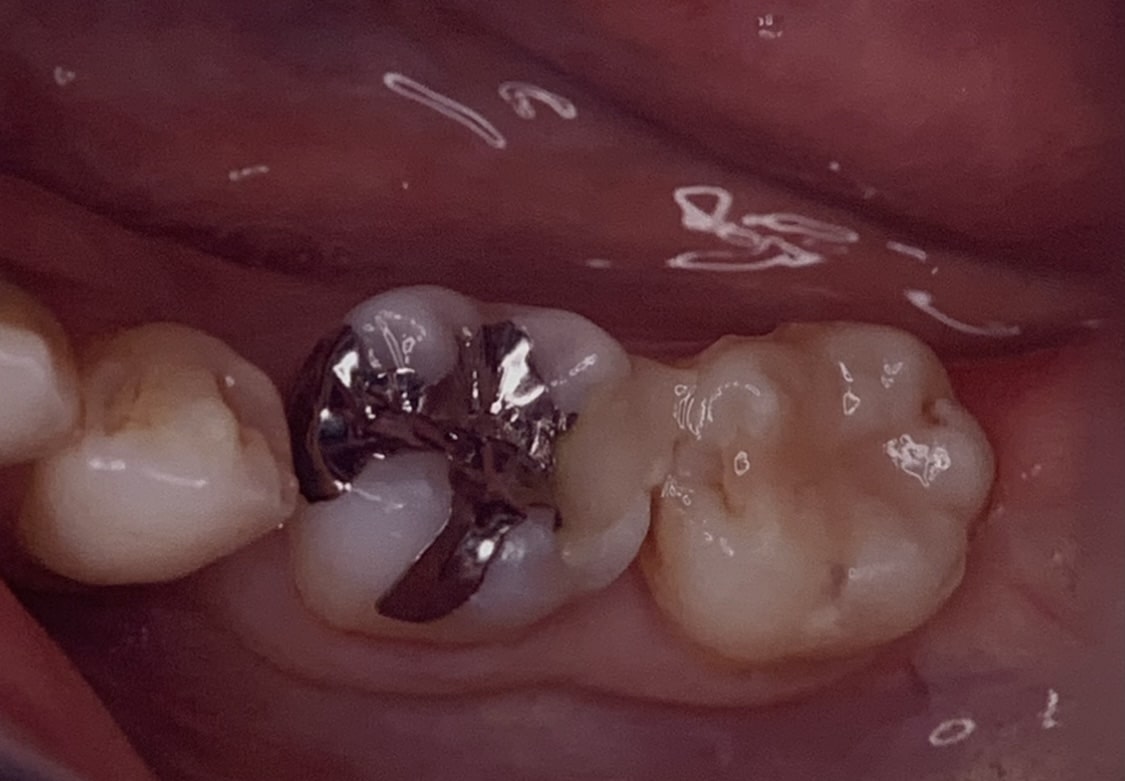

ちなみにこれは、セレックを使ったセラミック治療の統計ですが、当院では、患者様の希望にそって、銀歯もプラスチックもセットしています。

それらは保険で認められているものですから、悪いものではありません。しかし、当院でおこなっているジルコニアなどのセラミック治療と比べるともちという部分で差があるのは仕方がないことです。硬さが違い、プラークのつき方も、接着剤のつきも違いますから、口の中で安定してもつには限界もあります。

上のようなセラミックは、もともと長持ちというより見た目の向上という意味で患者様に選ばれてきました。しかし、当院で行うセラミック治療は少し違います。

見た目をこのように向上させることはもちろん、長く使えることを目標にしています。そのためにセラミックの精度は当然、接着や噛み合わせにまで留意して使っています。